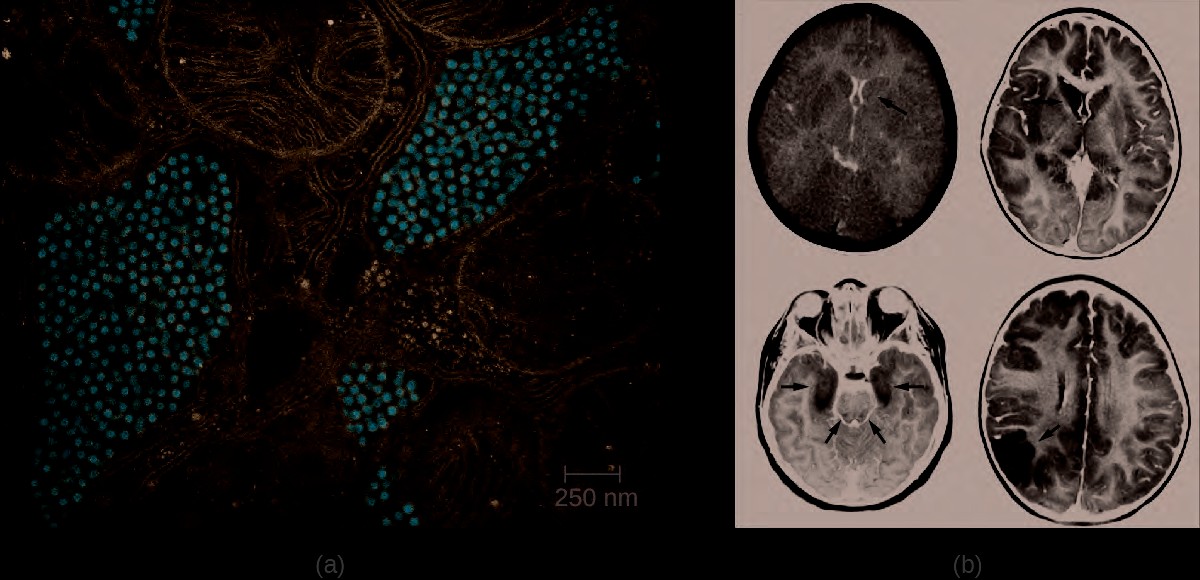

Figure 26.13 (a) A false color TEM of a mosquito salivary gland cell shows an infection of the eastern equine encephalitis virus (red). (b) CT (left) and MRI (right) scans of the brains of children with eastern equine encephalitis infections, showing abnormalities (arrows) resulting from the infection. (credit a, b: modifications of work by the Centers for Disease Control and Prevention)

Figure 26.14 (a) This colorized electron micrograph shows Zika virus particles (red). (b) Women infected by the Zika virus during pregnancy may give birth to children with microcephaly, a deformity characterized by an abnormally small head and brain. (credit a, b: modifications of work by the Centers for Disease Control and Prevention)